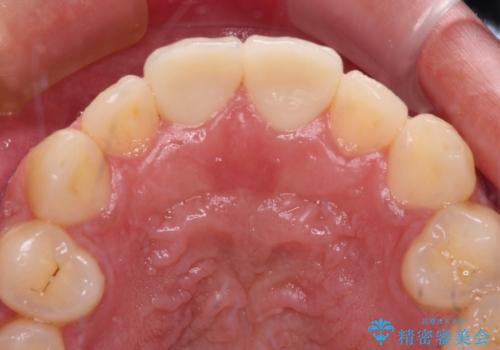

- 競技用自転車を運転中に転倒して前歯を強くぶつけ、欠けてしまったとのことで来院された患者様です。

近医にて欠けて部分を樹脂で修復してもらったものの、舌での感触が悪く、しみる感覚があるため、オールセラミッククラウンによる補綴治療を希望されていました。

仮歯に置き換え、しみる感覚が改善されてことを確認された後に、オールセラミッククラウンにて補綴治療を行うこととしました。